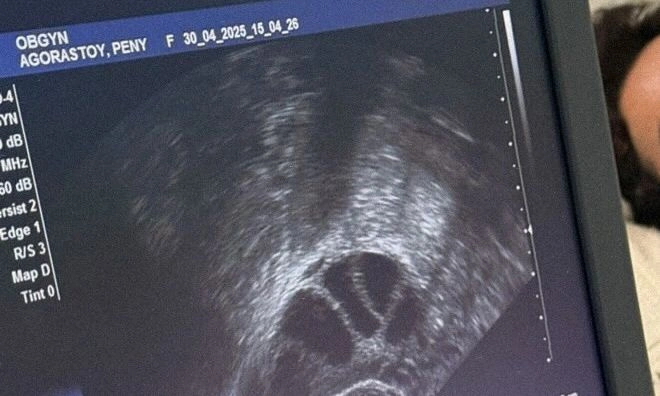

Όπως έγραψε και η ίδια στο μήνυμά της στο Instagram το οποίο και συνόδεψε με εικόνες από την όλη διαδικασία μέσα από το μαιευτήριο: «Πριν λίγες μέρες ολοκλήρωσα την κρυοσυντήρηση ωαρίων στο ΙΑΣΩ και νιώθω την ανάγκη να μοιραστώ αυτή την εμπειρία. Ήταν μια απόφαση που πήρα ενώ το σκεφτόμουν για χρόνια καθώς άκουγα και διάφορες απόψεις ! Η μητρότητα όμως δεν πρέπει να είναι θέμα πίεσης χρόνου,πρέπει να είναι επιλογή κ έχει πολλούς δρόμους. Επιλέγω λοιπόν μ αυτόν τον τρόπο να προετοιμάσω τον δικό μου με αγάπη και δύναμη.

Η κρυοσυντήρηση δεν είναι αναμονή είναι επιλογή, είναι φροντίδα για το μέλλον. Σήμερα, στην Ημέρα της Μητέρας, τιμώ κάθε γυναίκα που τολμά να κρατήσει ανοιχτή την πόρτα της δημιουργίας, με τον δικό της ρυθμό».